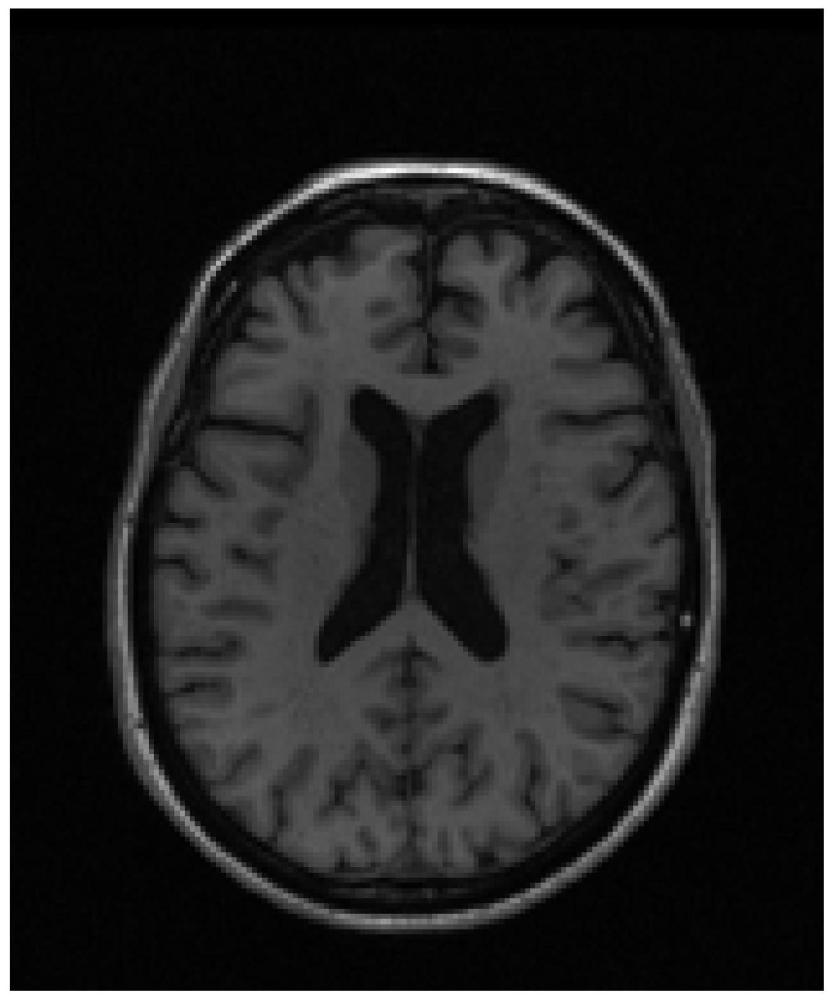

| 摘要: | 一种基于时序稀疏回归及加性模型影像相关性检测方法,包括4个步骤步骤。本发明通过上述4个步骤得到多个关于时间表型平滑函数及ROI的权重,从而通过多个SNP对表型的贡献描述特定区域得到大脑区域时间进展轨迹以及表型的区域差异的相关性。通过最小均方根误差RMSE作为特定大脑区域退变进展轨迹与模型是否匹配评价指标,本发明的RMSE为0.15,而现在技术模型基于时序稀疏加性模型的RMSE为1.14,稀疏加性模型的RMSE和组稀疏加性模型的RMSE都为1.33,因此本发明的效果更优。 | ||||